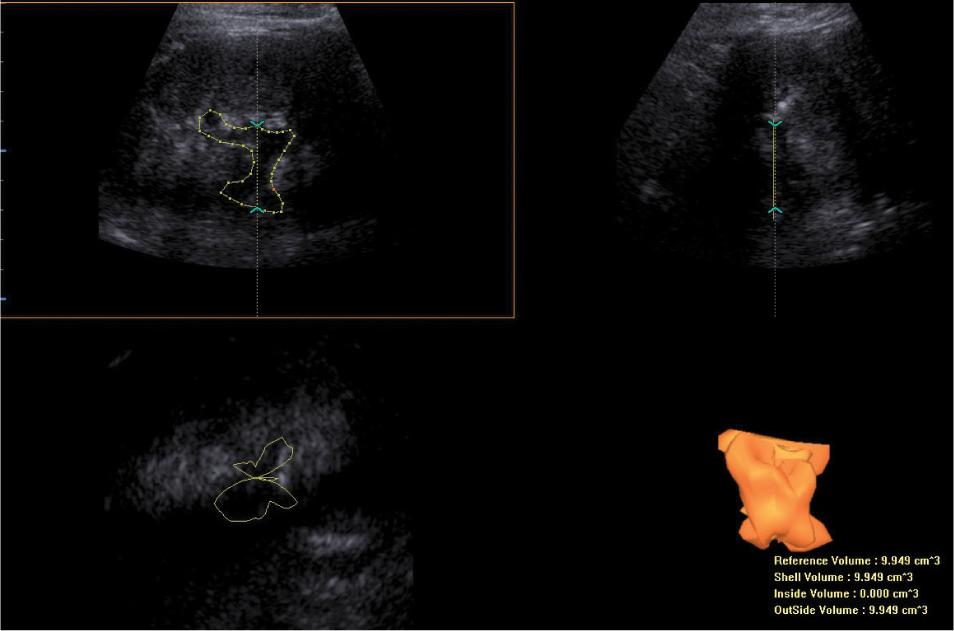

Fig. 4.

Three-dimensional ultrasound assessment of urine retention volume in the pelvicalyceal system. The VOCAL software has been used for volume calculations. Estimated pelvicalyceal volume = 9.95 cm3. The case presented in Fig. 1